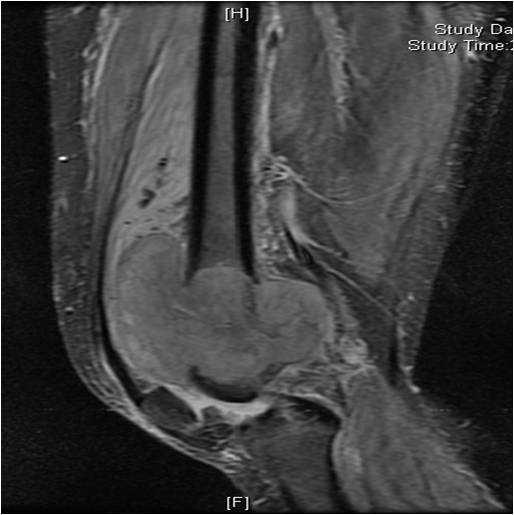

On radiographs, most MFHs of Bone are located in the metaphysis and present as purely osteolytic permeative lesions without a periosteal reaction and without mineralization (Fig. 1 &2). On MR images, MFH of Bone has ill-defined margins usually with cortical destruction of bone and extension into the soft tissues. It is usually hypo- or isointense to muscle on T1-weighted images (Fig. 3) and heterogeneous high intensity on T2-weighted images (Fig. 4-6).

Fig. 3: Coronal T1-weighted MR image of a Malignant Fibrous Histiocytoma of Bone demonstrates a lesion with intermediate signal similar to muscle in the distal femur. The lesion extends into the surrounding soft tissues.